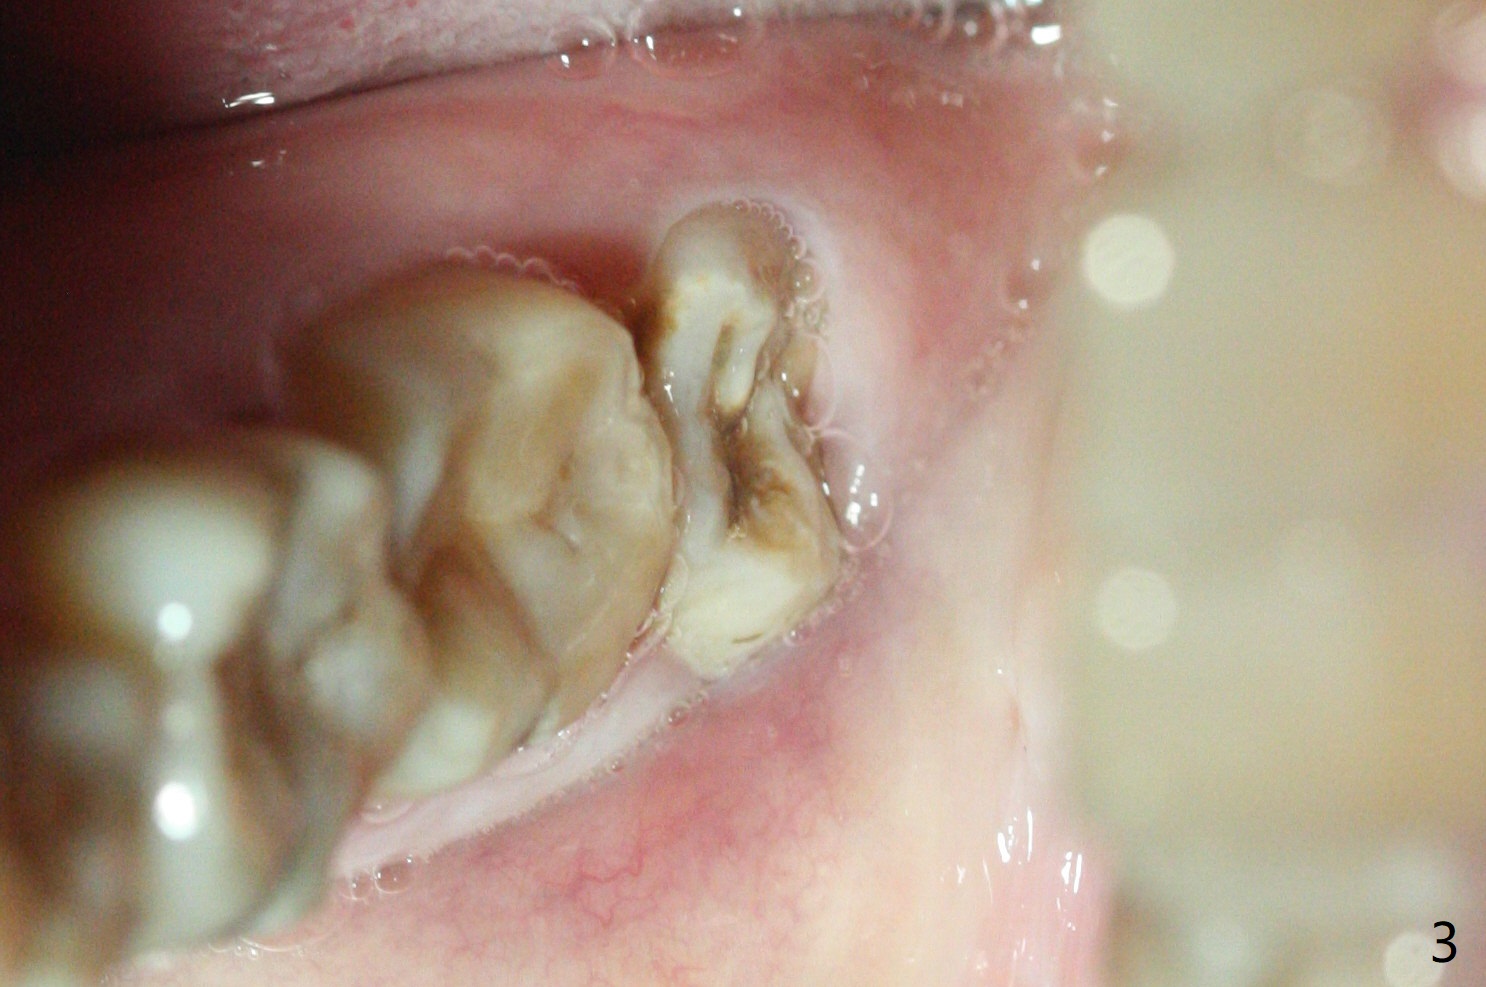

A 40-year-old man requests extraction of the teeth #17 and 32 (Fig.1). This case is designed to test that socket ossifies coronal when Collagen Plug is placed coronal. Release incision will be made both sides. Collagen plug will be placed at #32; none at #17. 4-0 PGA will be used to close the sockets. Photos will be taken immediate, 1 week, 1 month, and 3 months postop. PAs (sensor 1) will be taken immediate and 3 months postop. There is no wound dehiscence 1 week postop (Fig.6,7). The sockets reopen asymptomatic 3 weeks postop (Fig.8-11).